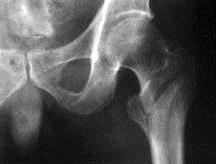

问题 病历摘要: 患者×××,男性,78岁,跌倒致伤右髋部后疼痛、行走障碍1天。查体:右髋部肿胀、触痛(+),右髋关节活动障碍,其余(-)。 该患者的诊断为: 提示: 该患者 X线如图:

选项 A、右髋关节结核 B、右股骨粗隆间骨折 C、右髋关节脱位 D、右股骨颈骨折 E、右髋关节骨关节炎 F、右髋关节化脓性关节炎 G、右股骨干骨折 H、髋臼骨折

答案 B